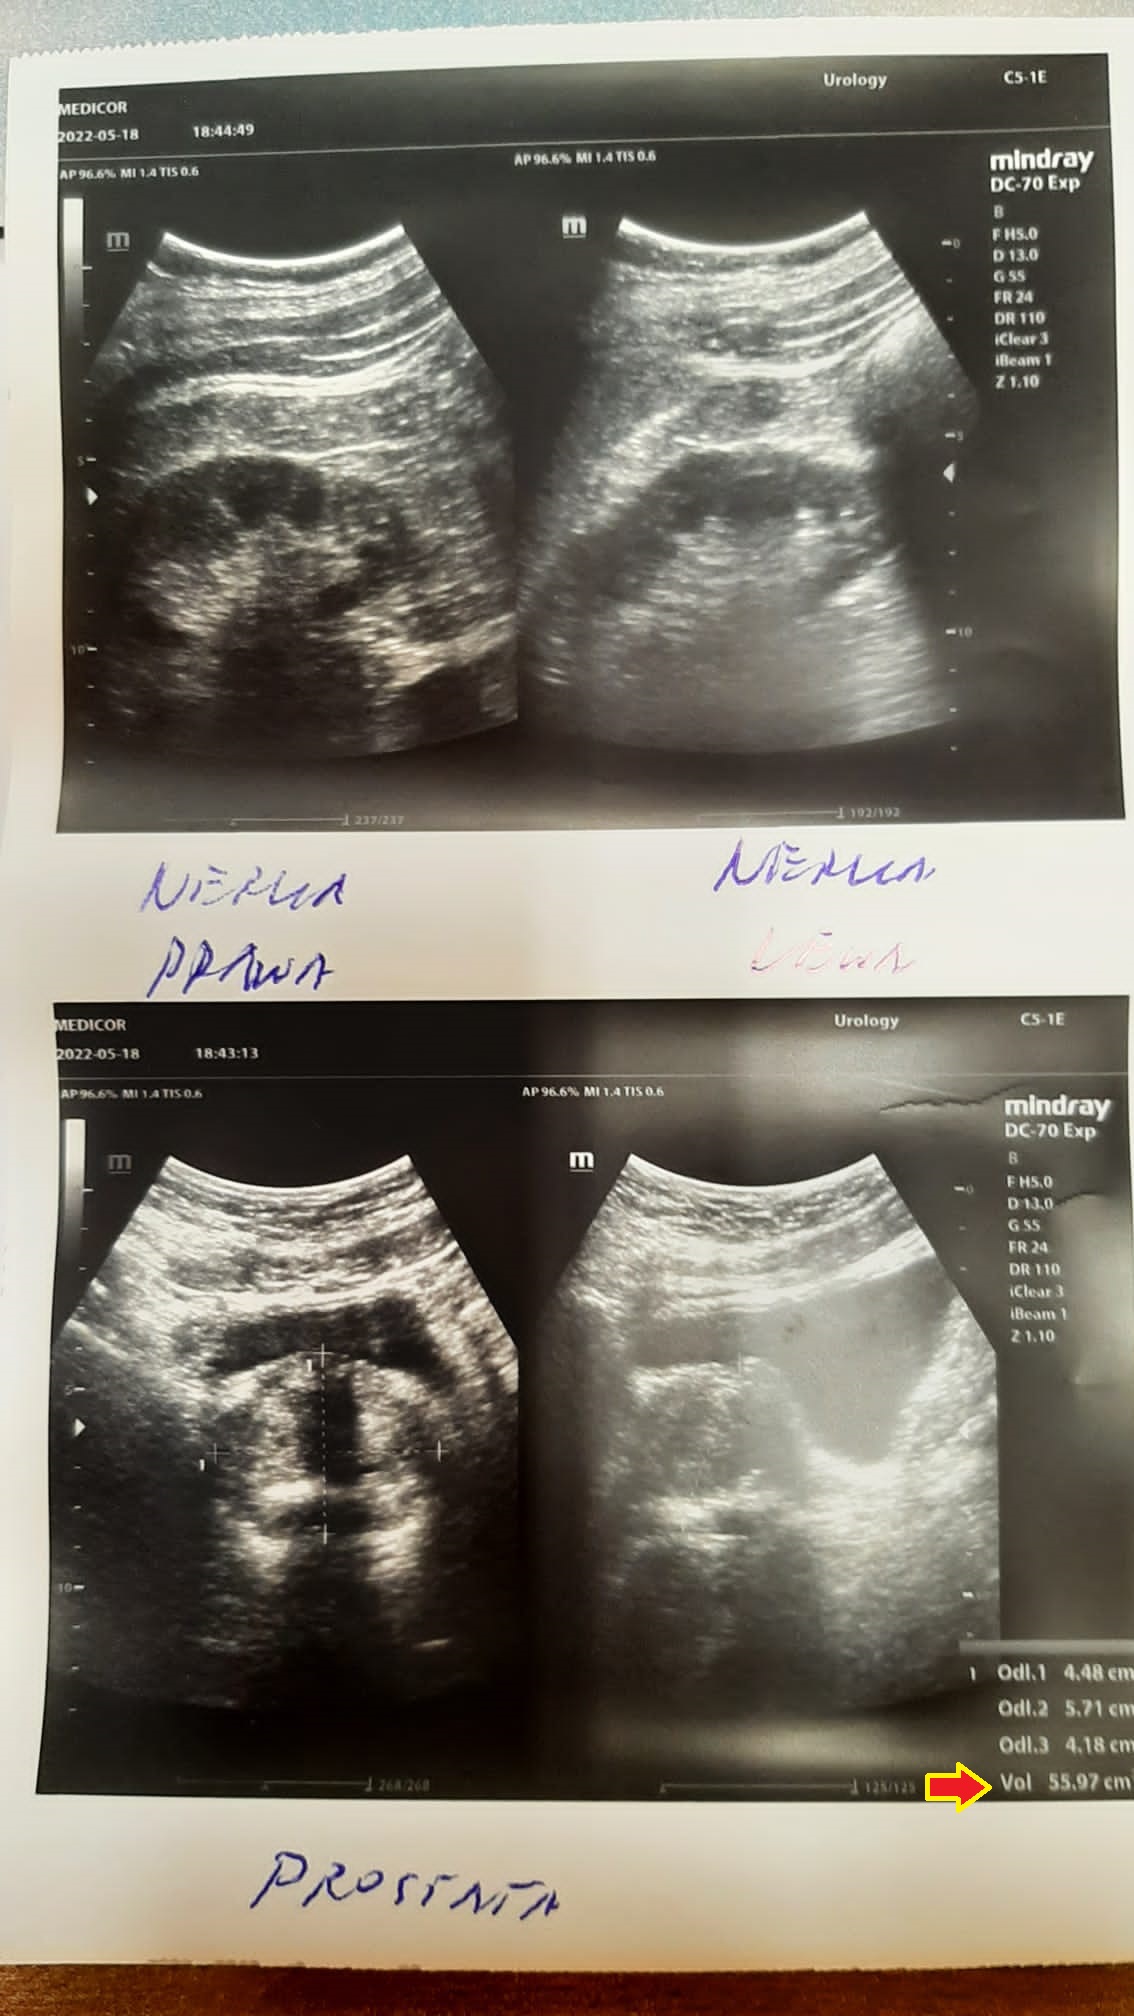

A 66-year-old man with a hypoechoic tumor measuring initially 16x10 mm and a prostate measuring 55x47 mm began treatment with the product. After three months, the first changes were observed: the tumor had shrunk to 6x7 mm and the prostate itself had decreased in size to 50x40 mm.

An examination after six months of treatment revealed no tumor, confirmed by imaging, and the prostate had reduced to the optimal size (48x61 mm), typical for this age group. The complete disappearance of the tumor in such a short time without the intervention of chemotherapy or radiotherapy indicates deep cellular regeneration. By stimulating mitochondria, the product delivers an increased amount of mitochondrial ATP, which leads to apoptosis of damaged prostate cells. The cellular regeneration process, by stimulating and protecting the structure and function of mitochondria, reverses uncontrolled cell division, indicating anti-cancer effects without toxicity.

A 50-year-old man with an enlarged prostate, although mild hyperplasia, experienced pain and discomfort when urinating. His prostate volume at diagnosis was 78.21 ml (78.21 cm3). After unsuccessful attempts with finasteride, an attempt was made to reduce the size of the prostate with a drug. As seen in follow-up ultrasound images, the reduction was significant, reaching 55.97 ml (55.97 cm3) after just 2.5 months of therapy.